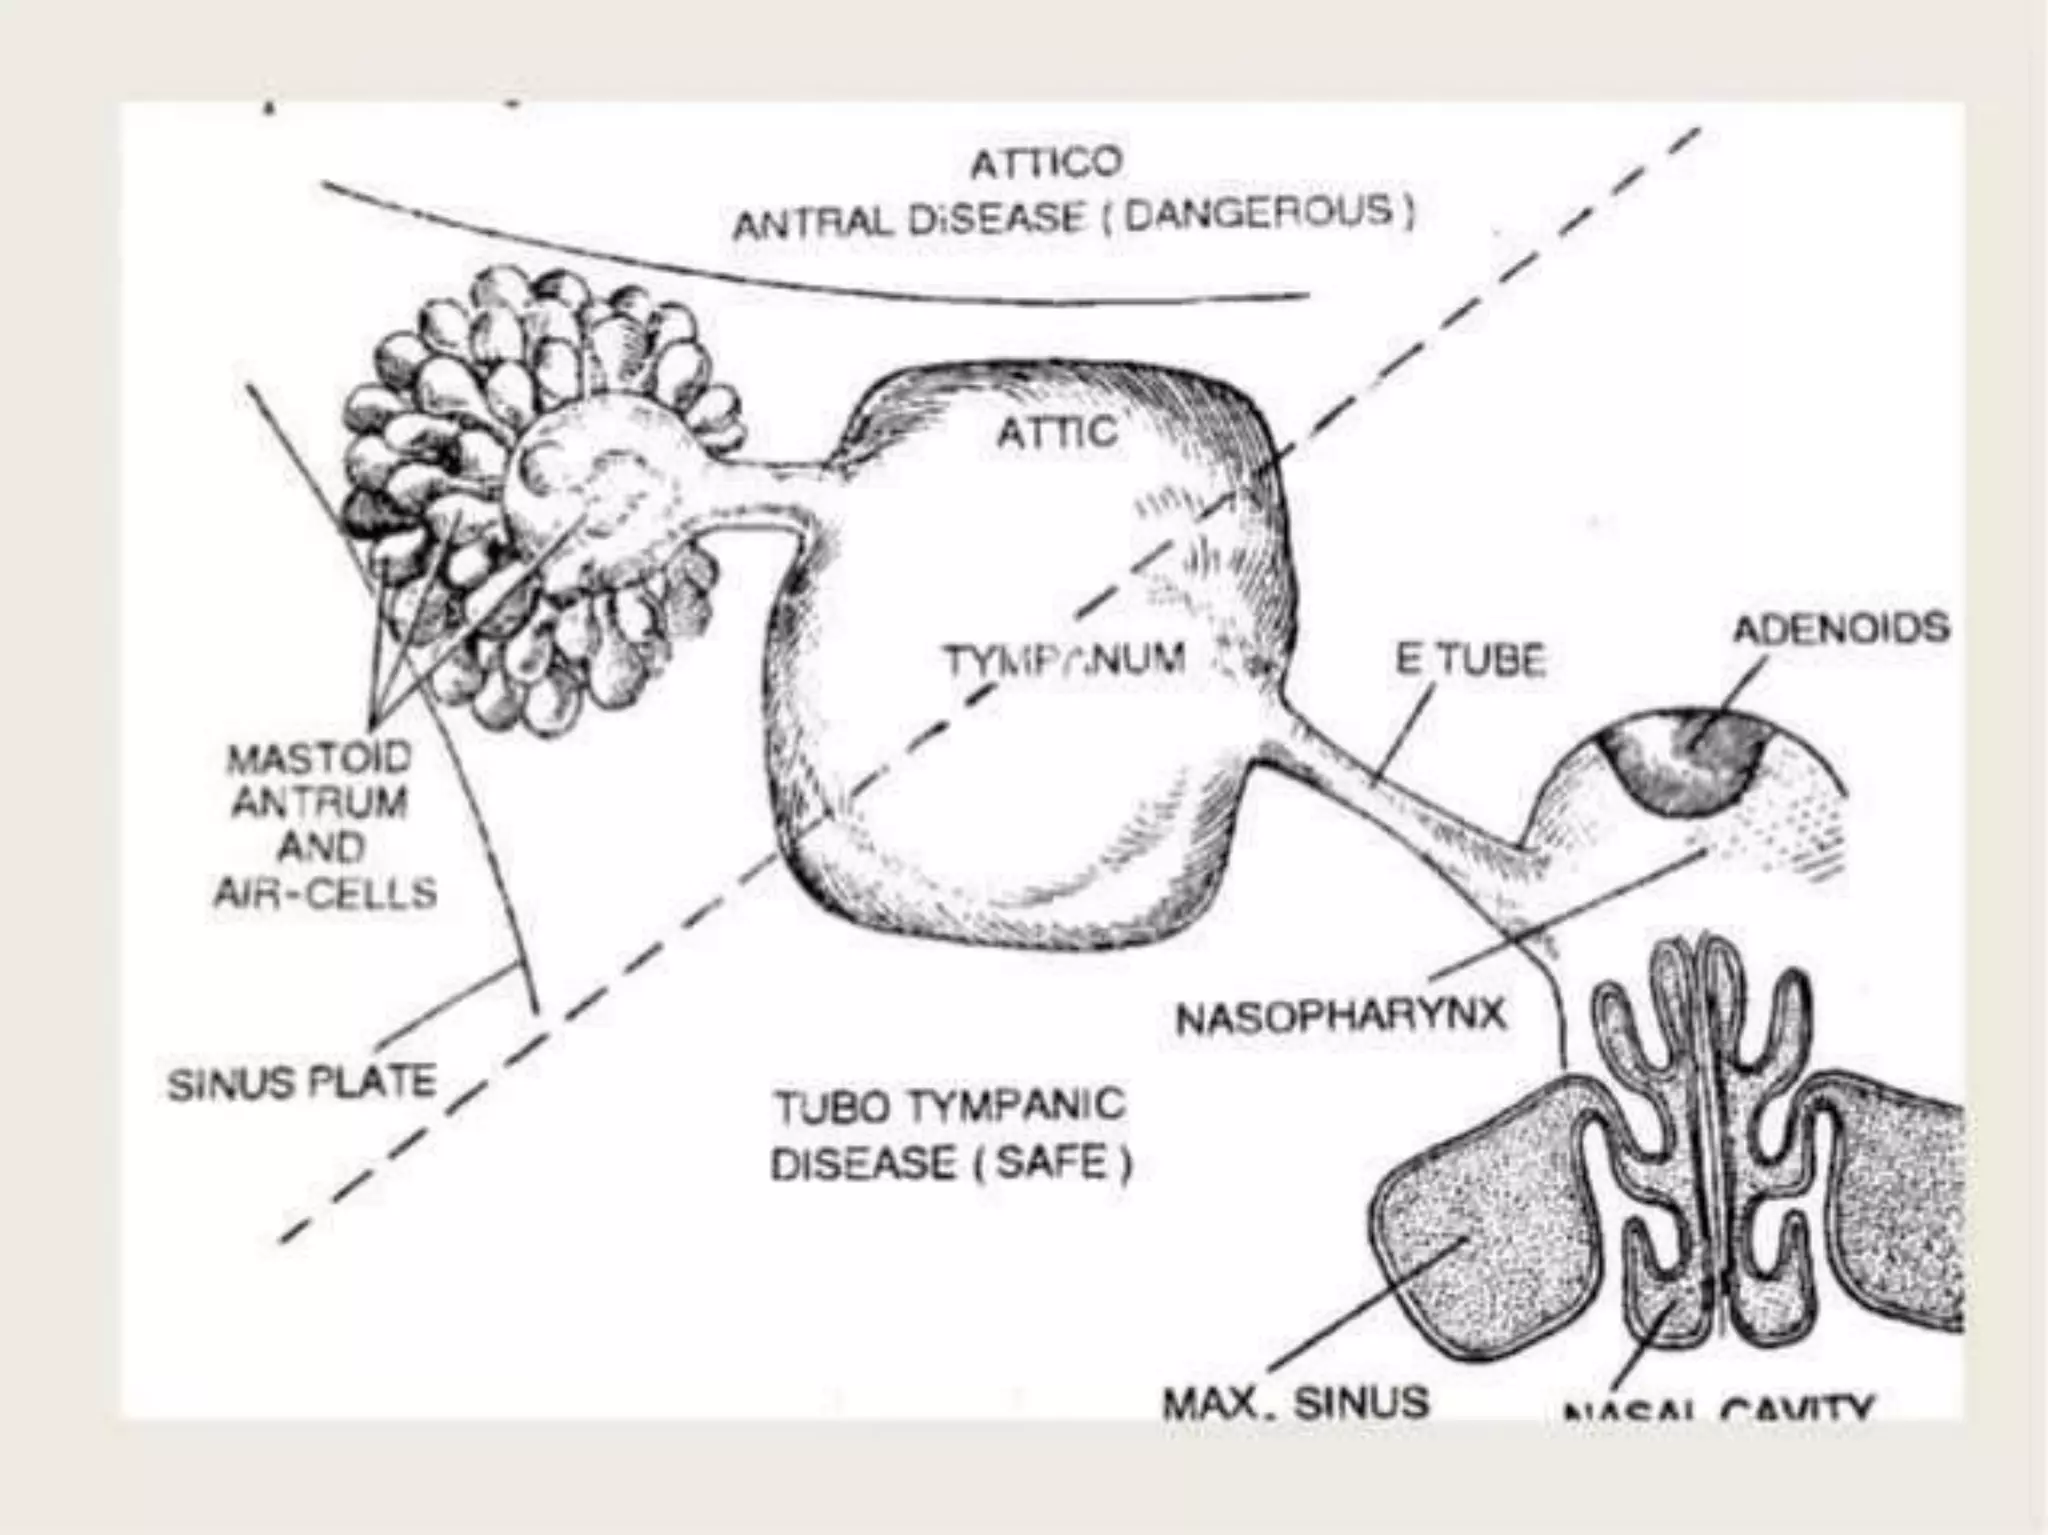

Chronic otitis media is a chronic inflammation of the middle ear and mastoid cavity that presents with recurrent ear discharge through a perforated eardrum. It has several subtypes depending on the state of the eardrum perforation and epithelium. It can be caused by prior acute otitis media, genetics, environment, eustachian tube issues, gastroesophageal reflux disease, craniofacial abnormalities, or immune deficiency.